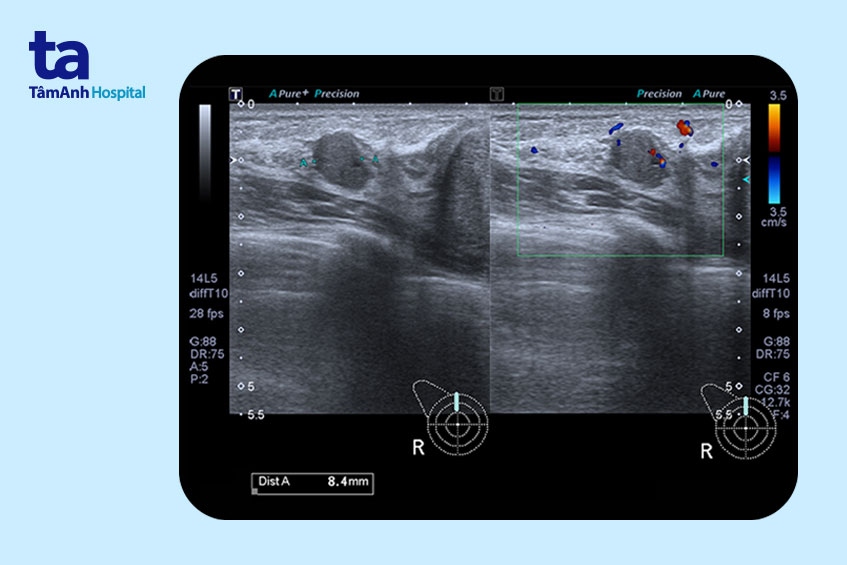

Bạn có thể nhận thấy ở vú có một khối u xơ bằng cách tự kiểm tra vú. U xơ tuyến vú có thể nhầm với u nang vú, ung thư vú, khối u diệp thể (phyllodes), u lympho vú, di căn của một khối u ở vị trí khác tới vú. Khi đi khám vú, nhận thấy người bệnh có các biểu hiện và triệu chứng của bướu sợi tuyến vú, bác sĩ sẽ chỉ định thực hiện các xét nghiệm sau.

Ngoài ra, bệnh viện trang bị đồng bộ máy móc, trang thiết bị hiện đại từ các nước Âu – Mỹ nhằm chẩn đoán bệnh chính xác nhất như máy siêu âm đàn hồi, máy chụp nhũ ảnh 3D, máy Hologic, máy chụp nhũ ảnh kỹ thuật số cắt lớp DBT, máy chụp cộng hưởng từ, máy CT 1975 lát cắt… giúp chị em cảm thấy an tâm và hài lòng khi đến khám và điều trị tại khoa Ngoại Vú.